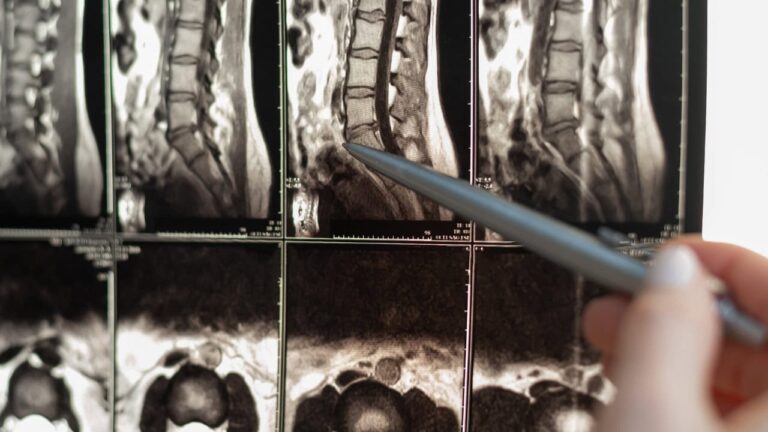

Σε ορισμένες περιπτώσεις, οι νευροπάθειες παγίδευσης εμφανίζονται στη σπονδυλική στήλη, όπως στις αυχενικές ή οσφυϊκές ριζοπάθειες. Αυτές οι καταστάσεις εμφανίζονται όταν οι νευρικές ρίζες συμπιέζονται, συχνά λόγω κήλης δίσκου ή εκφυλιστικών αλλαγών στη σπονδυλική στήλη. Ενώ οι διαταραχές αυτές μπορεί να φαίνονται διαφορετικές, μοιράζονται τον υποκείμενο μηχανισμό της συμπίεσης ή του ερεθισμού των νεύρων, που οδηγεί σε μια ποικιλία αισθητηριακών και κινητικών συμπτωμάτων.

7. Διαγνωστικές εξετάσεις

Τα προηγμένα διαγνωστικά εργαλεία, όπως η μαγνητική τομογραφία και η ηλεκτροδιαγνωστική, είναι χρήσιμα εργαλεία για την επιβεβαίωση της διάγνωσης σε πολύπλοκες περιπτώσεις. Η μαγνητική τομογραφία είναι χρήσιμη για τον εντοπισμό δομικών αλλαγών στους ιστούς που προκαλούν νευροπάθειες, ενώ οι μελέτες νευρικής αγωγιμότητας μπορούν να αξιολογήσουν τη λειτουργική κατάσταση των προσβεβλημένων νεύρων. Αυτή η χρονική συγκυρία αποτελεί σημαντική πρόκληση, καθώς οι ημικρανίες εκδηλώνονται κυρίως όταν τα άτομα είναι συχνά επικεντρωμένα στην καριέρα, την εργασία και την ανατροφή των παιδιών. Αφού φτάσουν σε αυτό το αποκορύφωμα, πολλοί άνθρωποι παρουσιάζουν μια σταδιακή μείωση της συχνότητας των ημικρανιών καθώς μεγαλώνουν, ιδίως οι γυναίκες, οι οποίες μπορεί να παρατηρήσουν μείωση των ημικρανιών γύρω από την εμμηνόπαυση.

Το μέλλον της διάγνωσης και της θεραπείας της νευροπάθειας παγίδευσης είναι πολλά υποσχόμενο, χάρη στην πρόοδο της απεικόνισης και της ιατρικής ακριβείας. Η μαγνητική τομογραφία υπερυψηλού πεδίου και η μαγνητική νευρογραφία ανοίγουν το δρόμο για ακριβέστερη διάγνωση, επιτρέποντας στους κλινικούς γιατρούς να απεικονίζουν τα νεύρα με πρωτοφανή λεπτομέρεια. Αυτές οι τεχνικές είναι ιδιαίτερα πολύτιμες για τον εντοπισμό λεπτών αλλαγών στη δομή των νεύρων που μπορεί να μην είναι ορατές με την παραδοσιακή απεικόνιση.